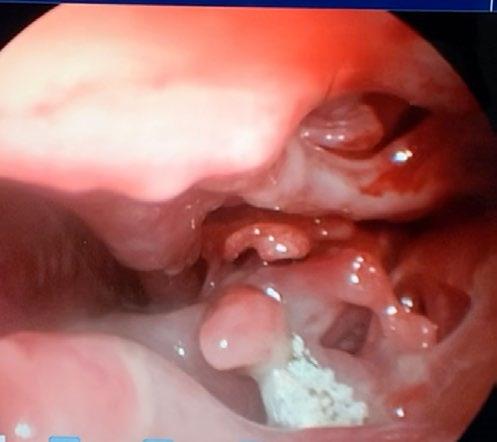

At the re-check, the owner reported no clinical response to the treatment trial so GA and rhinoscopy were planned as we are lucky enough to have a video endoscope at our clinic. Winnie was pre-medicated with methadone (0.3mg/kg) and medetomidine (0.005mg/ kg) intramuscularly. An intravenous catheter was placed, and anaesthetic was induced with 10 mg alfaxalone slowly intravenously to effect. A cuffed endotracheal tube was placed, and anaesthetic was maintained on isoflurane in 100% oxygen.

The most rostral aspect of the left nostril was ulcerated, and inflamed with purulent mucoid discharge which was difficult to direct the scope through. Once past it, there was extensive destruction of the nasal turbinates with a prominent fungal plaque (see Figure 1 and video). The right nostril was mildly inflamed; however, no plaques or destruction of turbinates was observed. We removed the plaque from the left nostril with forceps and placed it in a sterile container. There was also some tissue removed at the same time, half of which we placed in the sterile jar and half we placed in buffered neutral formalin on the off chance that if the culture of the plaque was

non-diagnostic, we could use the fixed sample to look for the presence of fungal hyphae, which, if present, can be seen on histopathology especially with special stains like PAS or Gomori silver.